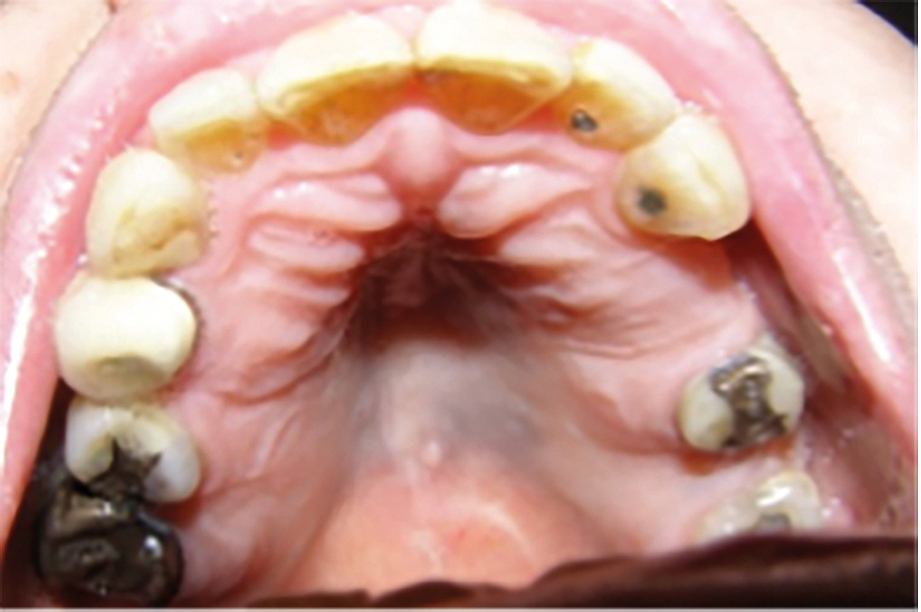

En biverkning som kan ses i anslutning till tandraden är gingival hyperplasi, som kan orsakas av behandling med kalciumflödeshämmare, men även av epilepsiläkemedel som fenytoin och immunhämmare som ciklosporin (Figur 2). I enstaka fall kan hyperpla­sierna bli så grava att de försvårar tandborstning, leda till tandlossning, bli kraftigt estetiskt störande och växa upp mot tuggytan [11]. Diagnosen kan bekräftas genom en biopsi som visar hyperplastisk vävnad. Risken för hyperplasier ökar vid bristande munhygien, varför detta är den första åtgärden. I många fall kan en fullständig utläkning ske enbart genom förbättrad munhygien. Vid kvarstående och/eller svåra besvär bör en bedömning göras av behandlande läkare om patienten kan dosminska eller byta läkemedel. Vid önskan om hjälp från tandvården torde de flesta kunna hanteras inom allmäntandvården. När behov av specialisttandvård uppstår, kan remiss skickas vidare till orofacial medicin.

Figur 2.